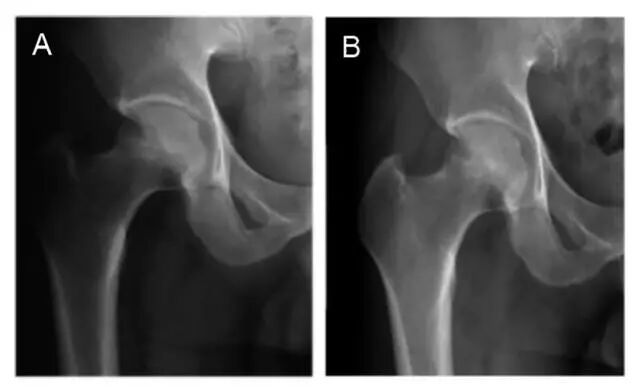

股骨头坏死是一个病理演变过程,初始发生在股骨头的负重区,应力作用下坏死骨骨小梁结构发生损伤即显微骨折以及随后针对损伤骨组织的修复过程。

造成骨坏死的原因不消除,修复不完善,损伤修复的过程继续,导致股骨头结构改变、股骨头塌陷、变形,关节炎症,功能障碍。股骨头坏死会引起病痛,关节活动和负重行走功能障碍。

结果发现,非置换的有50例,其中35例无塌陷(占54%)现象,即非置换率即髋关节保存率为77%;Harris髋关节功能评分大于75分的35例,平均为(79.5±11.9)分,临床成功率70%;目测类比评分(评测疼痛感)下降为(2.3±0.5)分,疼痛感缓解明显;需要辅助负重行走的情况从60.9%下降为18%。